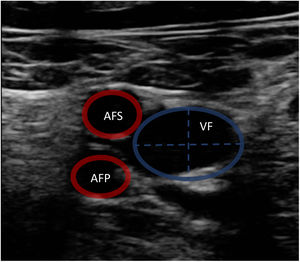

La ecografía vascular permite medir el diámetro vascular para elegir el tamaño óptimo de las cánulas (fig. 1). Para ello, se aplica la siguiente fórmula: tamaño cánula (French)=3×diámetro del vaso (mm). Se debe elegir el mayor tamaño de cánula tanto de drenaje como de retorno para proporcionar el mayor flujo posible. La punción vascular ecoguiada aumenta la seguridad y la tasa de éxito al primer intento, disminuyendo el riesgo de complicaciones locales (canalización arterial, canalización de la unión safeno-femoral o la transfijación del ligamento inguinal)11,20.

Durante la canulación, mediante la ecografía, podremos comprobar la inserción intravascular de las guías y posterior de las cánulas. En caso de uso de cánula de doble luz es indispensable la ETE, ya que puede haber complicaciones graves durante su implante (perforación de la AD o cava superior, migración al VD) y se debe comprobar una correcta orientación del flujo de retorno hacia la válvula tricuspídea21. En canulación con doble cánula simple, puede utilizarse la ETT o la ETE en ausencia de una buena ventana acústica. En la configuración fémoro-yugular, la cánula de drenaje debe quedar en la cava inferior por debajo de la vena suprahepática izquierda y el extremo de la de retorno a nivel de la AD (fig. 2) (suplementario 3). En la configuración fémoro-femoral, la cánula de drenaje debe quedar en la cava inferior y la de retorno en la AD. La distancia entre ambas cánulas debe ser al menos de 10cm para evitar la recirculación.